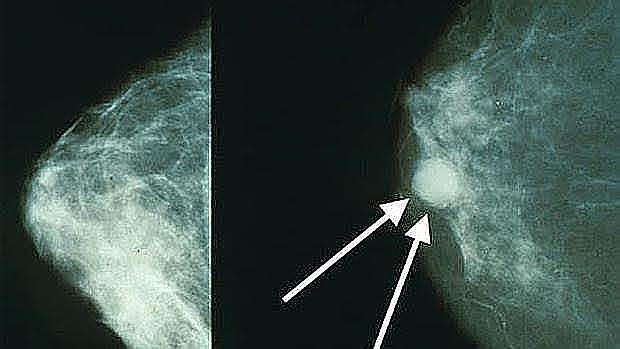

Metàstasi de mama

Científics de la Universitat de Tsukuba (Japó) van descobrir en ratolins un enzim (batejada com XIP) capaç d'impedir la metàstasi del càncer de mama